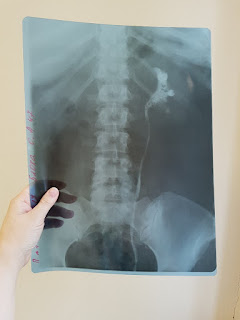

Это моя почка. Внутри пузырики - то осколки огромного камня, который мне разбили на мелкие кусочки. С 10 октября я уже перенесла две операции, октябрьскую еще более менее, но там у меня была температура каждый день почти 38 и меня госпитализировали вновь в ноябре, лежала в Самаре в клиниках мединститута. Ноябрьскую повторную операцию перенесла очень тяжело, еле откачали, был гипертоничский крис, два наркоза спинальных за 2 месяца это конечно ужас-ужас! Сейчас я со стентом, который стоит в почке, дабы выходил песок и мелкие осколки что остались после второй дробёжки. Стент (это типа трубки от капельницы), который уходит в мочевой... ни сидеть, ни стоять, ни дел никаких..все болит...чуть подвигаюсь, температура 38... уже жду когда с меня вынут эту фикню, правда каким будет качество жизни и как поведут себя почки я не знаю, но надеюсь, что буду мониторить свое здоровье.

Страшно девчата, вы себе не представляете как! чего я только в больнице не насмотрелась! берегите свое здоровье! В прошлом году когда мне делали по женски операцию, я думала страшно..не.. вот сейчас страшно, ибо почки потерять оказывается можно раз и все!... И самое обидное, что моей вины тут нет. Я каждый год прохожу обследование, мы с организации нашей платно проходим узи всех органов, куда смотрел узист? Случайно поехала в другой город и сделала там узи, диагноз то и выяснился.. а я все хандроз..хандроз..спину натираю мазями..оххо... камень у меня был размером почти 3см, закрыл лоханку, отток был нарушен, изменился и сузился мочеточник, теперь я осталась по сути инвалид, почка уменьшилась в размерах, мочеточник не станет более здоровым, теперь нужно будет часто сдавать анализы, делать узи и следить за собой. Я похудела на 15кг. Мне очень тяжело даются домашние дела, а еще ж на работу скоро выходить, я не представляю как я буду работать? Мне теперь многое нельзя: диета, ходить босиком, пить холодную воду из под крана, тока специальную или кипяченую..фу.., нельзя купаться, носить лейки, поливать из шланга...а как же мой огород и цветочки? кто будет деткам мыть бассейн... я в такой прострации живу. НО. жить надо, мне болеть и раскисать нельзя! у меня детки! и им нужна мама, здоровая)) Хорошо у нас няня, и я пока на больничном она нам помогает очень во всем! Сиделку наняли свекрови, ибо мне ходить за ней сил нет, а так она под присмотром, женщина очень порядочная нашлась. Супруг мой Семеныч держится, молодец! Пока я по больницам он с детьми и уроки, и уборка и стирка на нем, в магазин сбегать и на рынок, как кот Матроскин он у нас, хозяйственный)